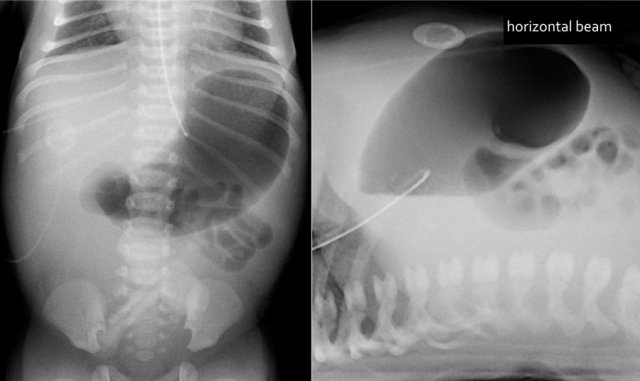

In this patient with NEC notice all the airbubbles in the wall of the bowel and within the liver.

Pneumoperitoneum in severe NEC.

Air can be seen on both sides of the bowel wall.

This is called the Rigler sign.